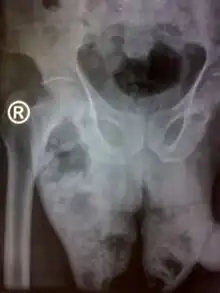

.JPG.webp)

Fournier gangrene is usually diagnosed based on symptoms and examination.[3] Common findings include swelling of the scrotum, fast heart rate, bad smelling discharge, crepitus, and fever.[1]

Laboratory tests and medical imaging may support the diagnosis, determine severity, and predict outcomes.[4] X-rays and ultrasound may show the presence of gas below the surface of the skin.[4] A CT scan can be useful in determining the site of origin and extent of spread.[4]